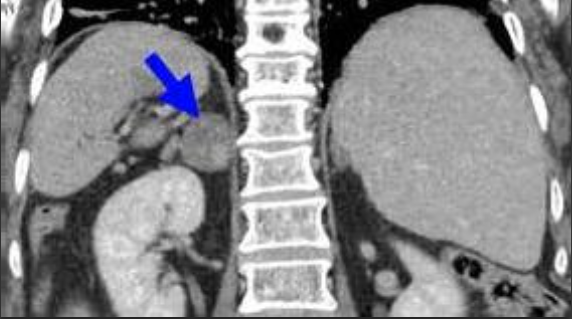

Снимок я нашёл в интернете ибо моего снимка нет уже очень давно

"В области межножкового пространства и тела правого надпочечника определяется объёмное образование круглой формы, размерами 18х21мм, с неровными чёткими контурами. Предположительно зрелая феохромоцитома".